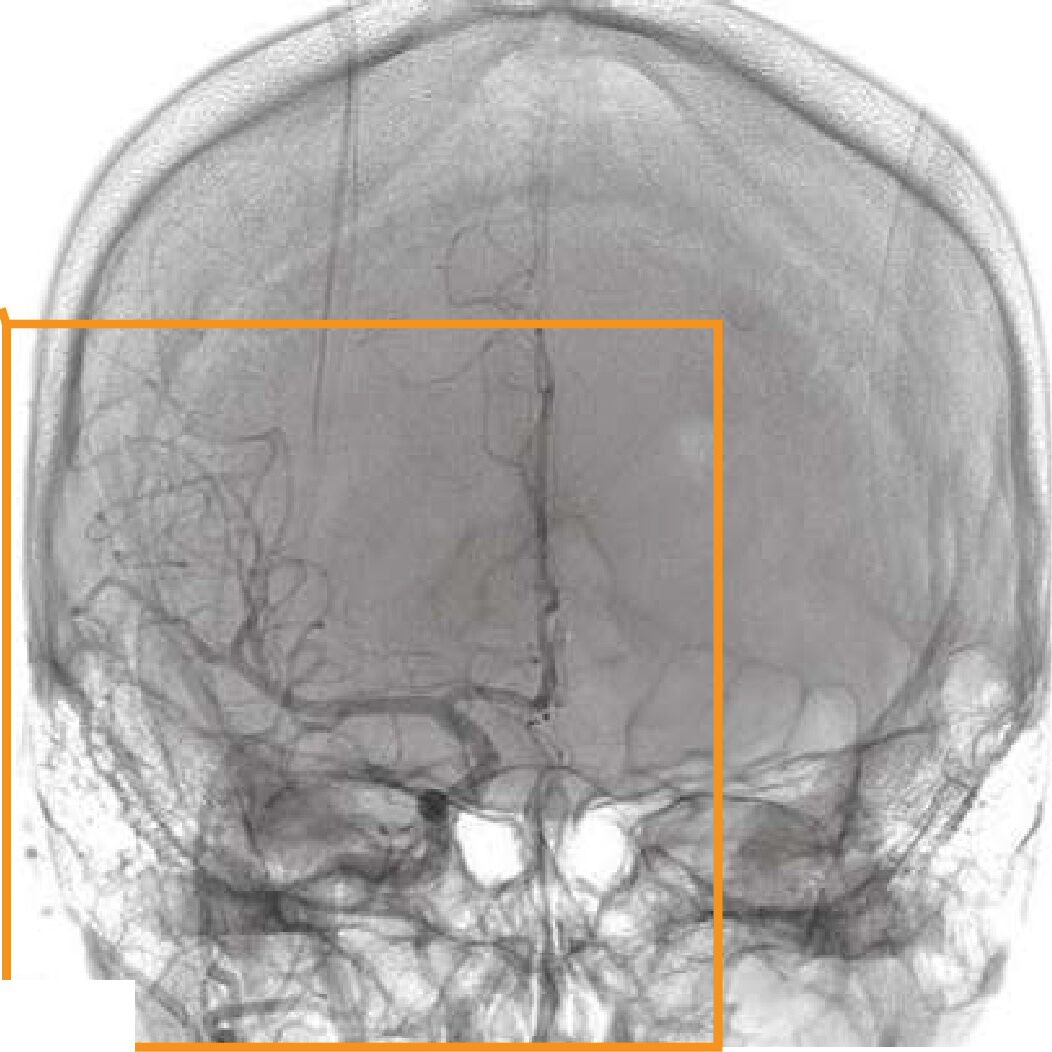

頭部X線写真(別冊No.7)を別に示す。撮影方法で正しいのはどれか。

- 1グリッドは使用しない。

- 2X線の射出点を鼻根とする。

- 340~50

kVの管電圧で撮影する。

- 4中心X線は検出器面に対し垂直に入射する。

- 5ドイツ水平線は検出器面に対し60度とする。